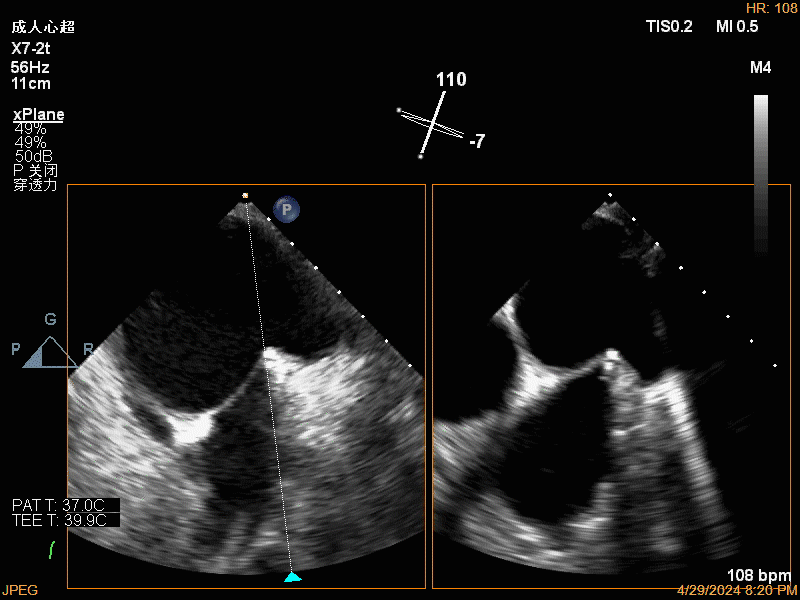

团队在反流最严重的2区精准植入1枚二尖瓣夹,即刻反流下降至微量,血压即刻上升20mmHg,跨瓣压差不升反降,由3mmHg降至2mmHg,改善效果明显,手术仅耗时一个半小时。 这是时隔四年继2020年指导开展区域内首例TAVR(经导管主动脉瓣置换)手术之后,陈茂教授再次带领华西团队,指导开展内自同城区域首例TEER术。陈茂教授对四院心内科心超图像的采集、房间隔穿刺的技巧、手术流程细节的把握、团队的默契配合、术前术后的管理表示称赞,鼓励四院心内科再接再厉造福区域患者。 患者为71岁老年女性,反复出现心累、气促已经超过10年,10多年来心衰的症状逐渐加重,间隔时间越来越短,且近1个月来已经3次因心衰住院,本次住院前已经无法耐受缓慢步行、如厕等日常生活,BNP超过了3000ng/ml。心电图为房颤,心超示左心室明显增大(65mm),重度二尖瓣反流(4+,CarpentierI+IIIb型),射血分数仅为31%。前叶长度:2.27cm且瓣尖增厚,后叶长度:1.14cm且局部钙化,瓣口面积:4.08cm2,反流宽度:1.7cm。患者及家属均拒绝外科开胸手术。 难点: 1.食道超声下该患者房间隔较厚较韧,且粗测高度仅为4.0cm,对穿刺的位置和技巧有较高要求; 2.左心扩大,反流宽度约17mm,放一个夹子可能不能有效解决反流,如放两个夹子需side by side 平行放置,但放置两个夹子有术后狭窄的风险; 3.前后叶对合似有间隙,若选用长宽夹子,会增加瓣叶张力,有瓣叶撕裂的风险,若选用短宽夹子,其捕获瓣叶的难度将增加; 4.患者心功能极差,手术需稳、准、快,不能耐受任何并发症风险。 影像资料 房间隔穿刺

![]() 关闭夹子 瓣膜夹释放后

![]() 释放后